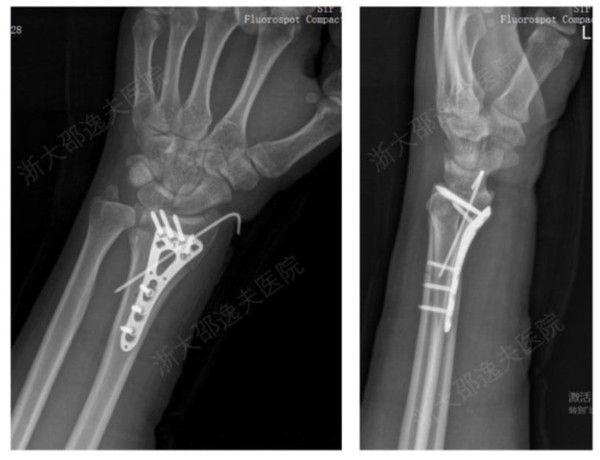

사진: CCTV 캡처

연구를 주도한 저장대학교 런런쇼 병원의 정형외과 전문의 판슌우 교수에 따르면 기존 골절 치료는 금속 고정법을 사용해왔다.

그는 "기존 골절 치료 방식은 금속으로 뼈를 고정해야 하는데 작은 뼛조각을 정확히 맞추기 어렵고 시간이 많이 걸렸다"며 "그 과정에서 뼛조각이 소실돼 뼈량이 줄고 결국 환자 삶의 질에도 악영향을 끼쳤다"고 설명했다.

실험 결과, 본-02는 최대 200kg 이상을 버틸 만큼의 접착 인장력을 보여 금속 고정 장치를 대체할 가능성을 입증했다. 특히 혈액이 많은 수술 부위에서도 단 2~3분 만에 뼛조각을 정밀하게 고정할 수 있는 것으로 확인됐다.

연구팀은 본-02를 활용할 경우 금속 이물질 반응 및 감염 위험을 줄이고, 수술 시간을 단축하며, 수술 중 손상을 줄일 수 있다고 전망했다.